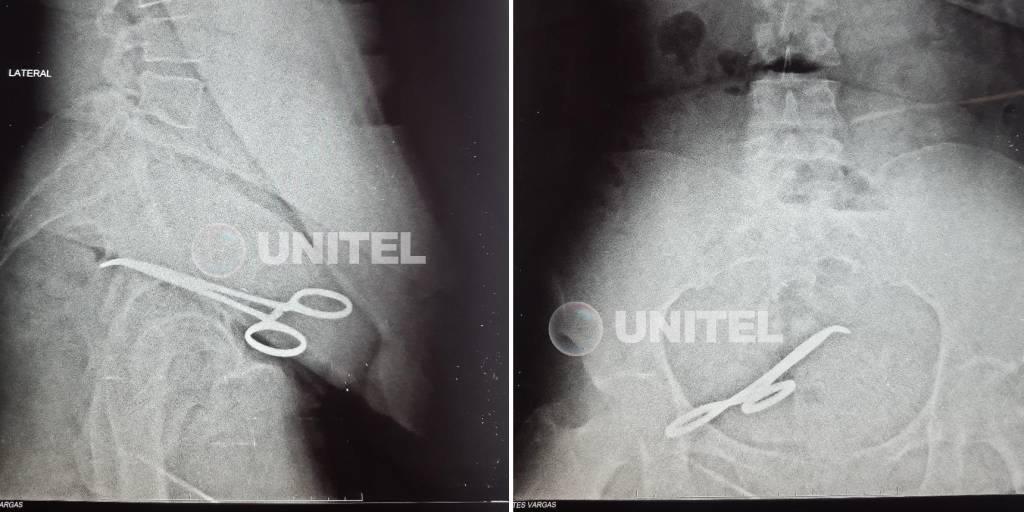

En la ecografía se evidencia la tijera quirúrgica

Luego de 10 días de hospitalización, fue dada de alta la mujer a la que hace tres meses se le dejó una pinza quirúrgica en el vientre luego de que fuera sometida a una cesárea. El hecho ocurrió en la ciudad de Santa Cruz.

Pese a ello, el bebé fue salvado y la madre fue dada de alta en los tiempos quirúrgicos establecidos. Sin embargo, tras molestias permanentes y consultas en otros centros, se le detectó la presencia de un objeto extraño en la cavidad, lo que derivó en una nueva cirugía, esto luego de tres meses de haberse ejecutado la intervención observada.